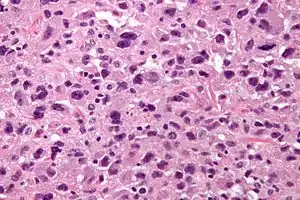

| Micrograph of undifferentiated pleomorphic sarcoma (H&E stain) | |

UPSs are, by definition, undifferentiated, meaning (as the name implies) that they do not bear a resemblance to any normal tissue.

The histomorphology, otherwise, is characterized by high cellularity, marked nuclear pleomorphism, usually accompanied by abundant mitotic activity (including atypical mitoses), and a spindle cell morphology. Necrosis is common and characteristic of high-grade lesions.